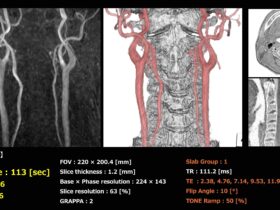

Segmented TOF法を使って11...